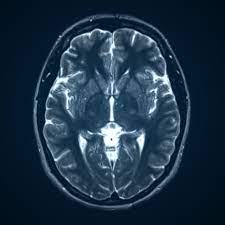

MRI for the Head

If you’re experiencing symptoms such as severe headaches, blurred vision, or confusion, your doctor may recommend an MRI scan of the brain. This type of MRI scan can help diagnose a variety of conditions, including strokes, tumors, aneurysms, and multiple sclerosis.

An MRI scan of the brain is painless and does not involve any radiation. It’s also very safe, although people with certain metal implants, such as pacemakers, may not be able to have an MRI scan.